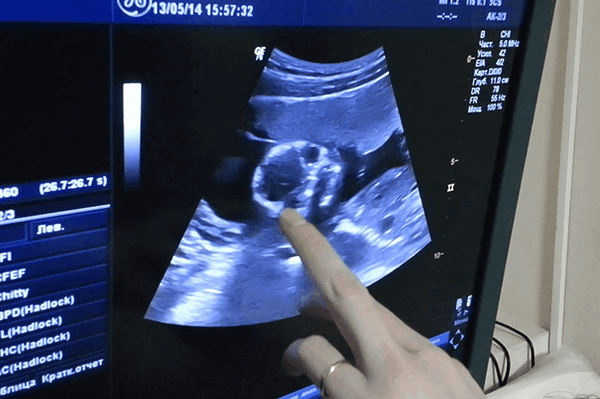

УЗИ в акушерстве и гинекологии

Акушерство. Приоритетное использование метода в акушерстве связано с отсутствием ионизирующего излучения и возможностью поэтому динамического наблюдения за пациентом. Техническая простота также относится к преимуществам УЗИ. Важной оценкой эффективности данной диагностики является снижение заболеваний и смертности матери и плода, что может быть достигнуто за счет более точного определения срока беременности и родов, выявления аномалий развития плода и многоплодия. Особое место занимает ранняя диагностика внематочной беременности.